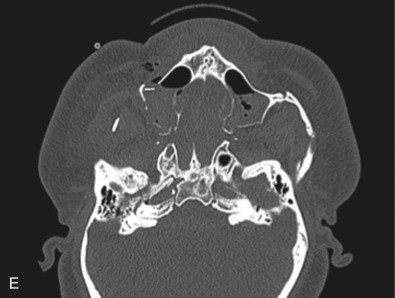

Le Fort III fractures generally consist of a combination of fractures that involve the palatine bones, the maxilla, the pterygoid plates, the nasal bones, lacrimal bone, and zygomas; they essentially separate the face along the base of the skull. The fracture pattern extends through the nasofrontal suture along the medial wall of the orbit, through the inferior orbital fissure and the lateral orbital wall to the zygomaticofrontal suture. In addition, the zygomaticotemporal suture is separated. The fracture extends across the sphenoid bone resulting in dysjunction at the pterygoid plates ( Figs. 1.13.16 and 1.13.17 ). The septum is separated from the cribriform plate of the ethmoid. Pure Le Fort III fractures are rare, and in actuality, most are ZMC fractures in conjunction with Le Fort I and II fractures lending the appearance of a comminuted “Le Fort III.” The force is delivered from the orbital level, resulting in craniofacial dysjunction. The fracture is generally more comminuted and more extensive on the side of force application.